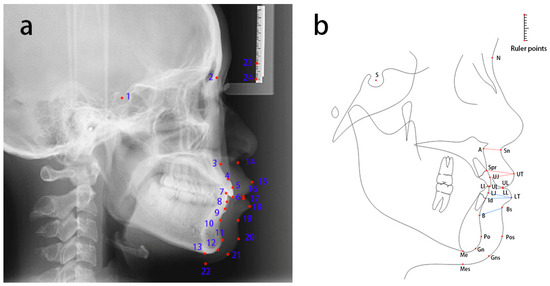

| No. | Landmarks |

|---|---|

| 1 | Sella (S) |

| 2 | Nasion (N) |

| 3 | Subspinale (A) |

| 4 | Superior prosthion (Spr) |

| 5 | The most labial surface of the upper incisor (UJ) |

| 6 | Upper incisor (UI) |

| 7 | Lower incisor (LI) |

| 8 | The most labial surface of the lower incisor (LJ) |

| 9 | Infradentale (Id) |

| 10 | Supramental (B) |

| 11 | Pogonion (Po) |

| 12 | Gnathion (Gn) |

| 13 | Menton (Me) |

| 14 | Subnasale (Sn) |

| 15 | Labrale superius (UT) |

| 16 | Stomion superius (UL) |

| 17 | Stomion superius (LL) |

| 18 | Labrale inferius (LT) |

| 19 | Inferior labial sulcus (Bs) |

| 20 | Pogonion of soft tissue (Pos) |

| 21 | Gnathion of soft tissue (Gns) |

| 22 | Menton of soft tissue (Mes) |

| 23 | Ruler point 1 |

| 24 | Ruler point 2 |